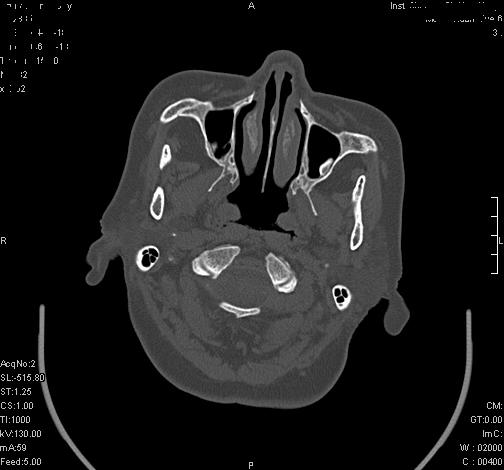

上次发的片子,不够细微。误导了大家,请大家再重新看一下,思路会更清晰。

双侧上颌窦上部黏膜明显增厚、窦腔缩小,偏后侧窦壁骨质毛糙、模糊,窦腔内见条块状钙化。结合双侧鼻甲黏膜明显增厚,以及临床症状,

考虑:双侧上颌窦霉菌性鼻窦炎

双侧上颌窦密度增高,粘膜增厚,内见条片状钙化,窦壁无增生与破坏征象,双侧鼻甲粘膜肥厚.

意见:双侧霉菌性上颌窦炎.

温习:真菌性鼻旁窦ct特征 1)非侵袭性病变者可涉及到鼻腔和鼻窦,多为单侧,上颌窦最多见.2)ct示窦腔内软组织增生影,可呈息肉状,+c可强化3)增生软组织影内可见散在斑片状或沙砾状钙化区,此为其典型特点,4)

非侵袭性病变可见窦壁骨质增生,破坏少见;侵袭性病变可见窦壁骨质破坏.